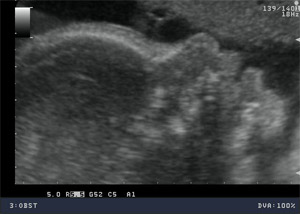

USG CIĄŻY

We wczesnej ciąży najlepszy obraz daje sonda dopochwowa. Badanie musi odpowiedzieć nam na pytanie czy ciąża jest pojedyncza, czy mnoga? Czy jest żywa? Czy jest prawidłowo umiejscowiona? Z tego względu badanie USG przewyższa znacznie testy ciążowe. Od 4 miesiąca stosowane są przede wszystkim sondy przez brzuszne. Aktualnie Polskie Towarzystwo Ginekologiczne zaleca wykonanie w ciąży prawidłowej trzech badań USG: około 11 – 13+6 tygodnia ciąży, około 18 - 24 tygodnia ciąży oraz 28 - 32 tygodnia ciąży. Każde z tych badań ma celu ocenę aktualnego rozwoju i dobrostanu płodu. W niektórych przypadkach możliwe jest przewidywanie zagrożenia ciąży na kilka tygodni wcześniej.

USG prenatalne 11 - 13+6 tydzień ciąży

Jest to badaniem przesiewowym wykonywanym między 11 a 13+6 tygodniem (13 tygodni i 6 dni), które ma ułatwić wykrycie zespołu Down’a (trisomii 21 pary chromosomów) i trisomii 18 pary chromosomów. Badanie ultrasonograficzne wraz z badaniami biochemicznymi (białko: PAPP-A oraz wolną podjednostką beta hCG) określa ryzyko wystąpienia wad rozwojowych płodu, pozwala na ocenę rozwoju płodu. W pewnych przypadkach zalecane są dalsze, bardziej szczegółowe badania – oznaczanie DNA płodowego lub amniopunkcję genetyczną i prenatalne badanie ultrasonograficzne między 18-24 tygodniem ciąży.